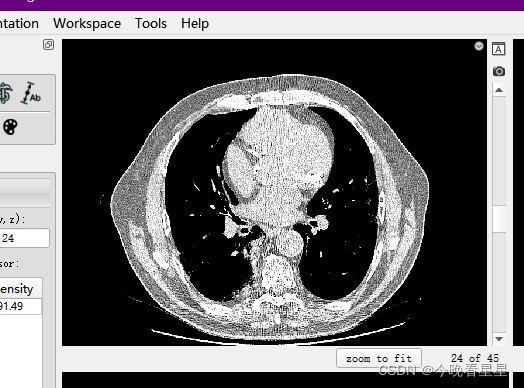

对于处理DICOM的软件有众多,本文章采用ITK-Snap来进行介绍。ITK-Snap的主要功能是对医学图像进行分割,包括2D与3D的分割,包括人工分割与半自动分割。本文主要介绍ITK-Snap的基本使用,包括基本功能的介绍,医学图像的查看以及医学图像的标注

1.1 ITK-Snap视图介绍

在刚开始使用软件的时候,可能上来就被该软件的视图搞蒙了,类似于咱们数学上的三视图,但是他是从CT扫描的视角观察的

三个切片窗口分别为:

- 轴向面(Axial)

- 矢状面(Sagittal)

- 冠状面(Coronal)

常用的有轴向面与冠状面,可以帮助我们进行空间上的定位与标注

显示一个主图